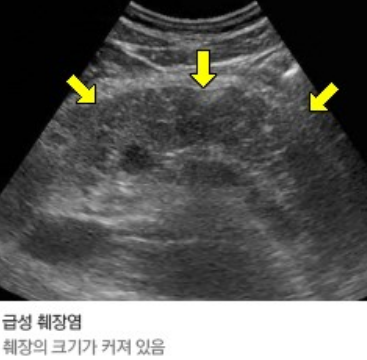

간의 실질 크기와 간내 혈관의 크기, 간의 미만성 또는 국소적 병소, 담낭 및 담관의 구조 및 확장 여부를 알 수 있고,